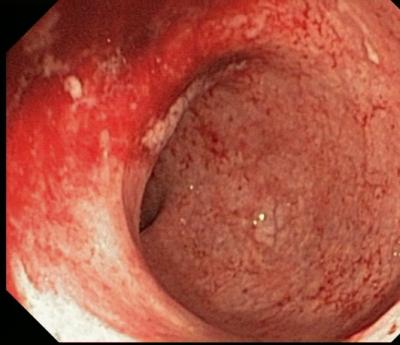

Анатомические и функциональные особенности толстого кишечника визуализируются его при контрастной ирригоскопии. Колоноскопия позволяет досконально изучить состояние слизистой на всем протяжении толстой кишки. Кроме того, проведение колоноскопии позволяет взять биоптаты слизистой кишечной стенки для дальнейшего гистологического исследования.

С диагностической целью при колитах показана ректороманоскопия, где определяется гиперемия и отек слизистой дистальных отделов толстой кишки, на стенках кишки видно большое количество слизи, а в более тяжелых случаях - гноя; нередко находят эрозии, изъязвления и кровоизлияния.